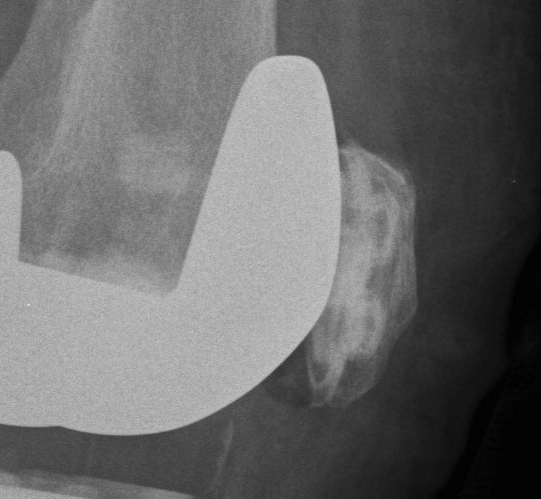

3. Patella fracture

- caused by excessive bone resection & holes in patella for fixation

Over-resection

- predispose to fracture

- ensure 15mm minimum